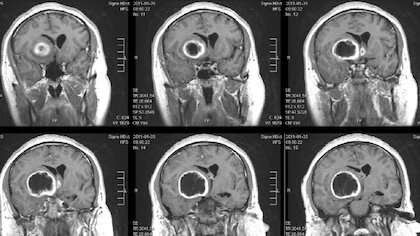

A combination of immunotherapy agents that encourages some immune cells to eat cancer cells and alert others to attack tumors put mice with a deadly type of brain cancer called glioblastoma into long-term remission, a new study led by UT Southwestern scientists suggests. The finding, published online March 20, 2020, in Nature Communications, could lead to new therapies that may significantly extend survival for human glioblastoma patients, which stands at an average of 15 months after diagnosis even with current state-of-the-art therapies.

Some pharmaceuticals in development aim to boost the innate immune system’s action against cancer by blocking CD47, a protein that many cancer cells display on their surfaces that functions as a “don’t eat me” signal. Glioblastoma (GBM) – the most common primary central nervous system malignancy in adults and a cancer that Jiang frequently treats in clinic—often displays substantially elevated amounts of CD47 on its tumor cell surfaces, with higher amounts generally suggesting worse outcomes for patients. But these drugs have had mixed results in clinical trials, Jiang says; although they’ve shown promise for blood cancers, such as leukemias, their performance for solid tumors has been disappointing.

When the researchers tested this combination therapy in a mouse model of GBM, it successfully shrank tumors and extended life. However, in time, the tumor cells developed a different way to evade the immune system by boosting their production of a protein called PD-L1, which shields them from T cell attack. Thwarting this move, the researchers added an antibody against this protein called anti-PD-1. Together, this three-part regimen—anti-CD47 antibodies, TMZ, and anti-PD-1 antibodies—dramatically extended survival. About 55 percent of these animals did not die over the course of the study, a scenario akin to long-term remission in patients, Jiang says. He and his colleagues hope to test this approach in humans soon in a clinical trial, he adds.